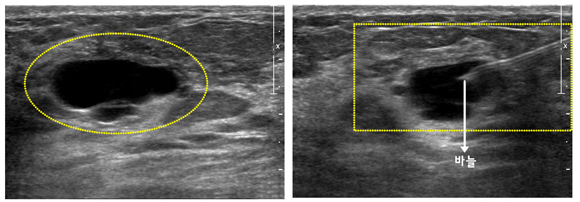

가는 주사 바늘 (20-25게이지)을 병변 부위에 찔러 소량의 세포를 얻어 현미경으로 암의 유무를 검사하는 방법입니다. 간편하고 정확하며 큰 합병증 없이 환자에게 고통을 덜 주는 방법입니다. 주사 바늘로 하는 조직 검사의 경우 잘 만져지는 병소에 대해서는 별 무리 없이 여러 번 검체를 채취할 수 있으나 잘 만져지지 않는 병소의 경우 실시간으로 초음파 영상을 보면서 바늘을 병변 내에 위치시킨 후 흡인합니다. 이 검사로 약 90% 이상에서 암을 정확하게 진단해 낼 수 있습니다.

장점으로는 시술이 빠르고 통증이 적고 안전하며 혈종의 발생이 적고 세침의 경로를 따라 암 전이의 가능성이 적다는 점이 있습니다. 물혹의 경우 주사기로 액체를 흡입함으로써 진단 및 치료가 가능합니다. 단점으로는 충분한 양의 조직을 얻을 수 없어 정확한 진단을 내리는데 한계가 있고 숙련된 세포병리 전문가가 필요하며 유방암의 조직학적 등급을 알 수 없다는 점입니다. 또한, 침습성 유방암과 상피내 유방암을 구분하기 어렵습니다.

[ 세침흡인 세포검사 초음파 사진과 세침흡인 세포검사 시술 사진 ]